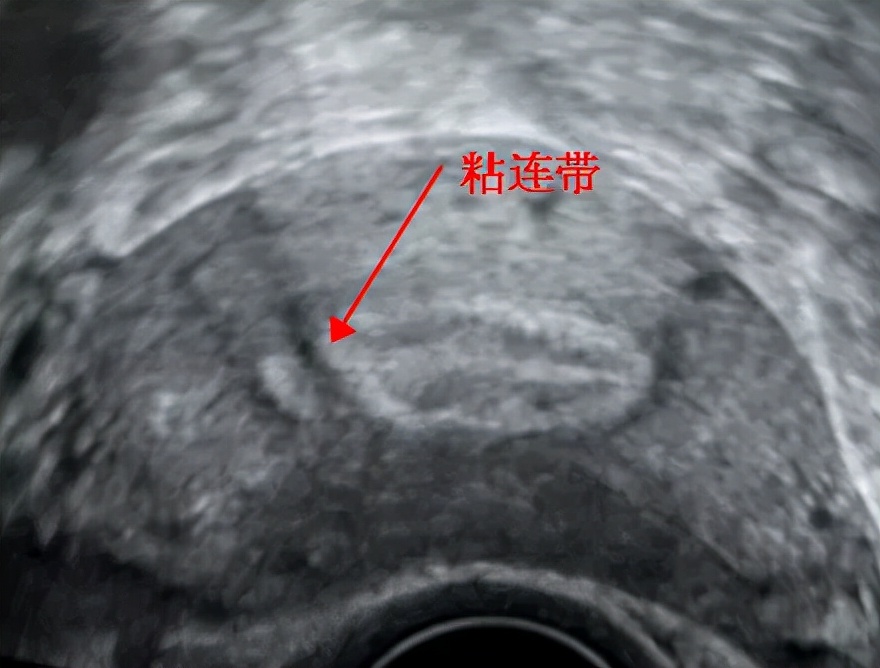

内膜本该连续的地方却见到一处连续性中断的地方

箭头所指就是粘连处

这都是在内膜有一定厚度和形态且粘连程度较明显的情况下,超声可以看到的间接征象。现在不止二维的超声可以检查宫腔粘连,三维超声也可筛查出宫腔粘连。